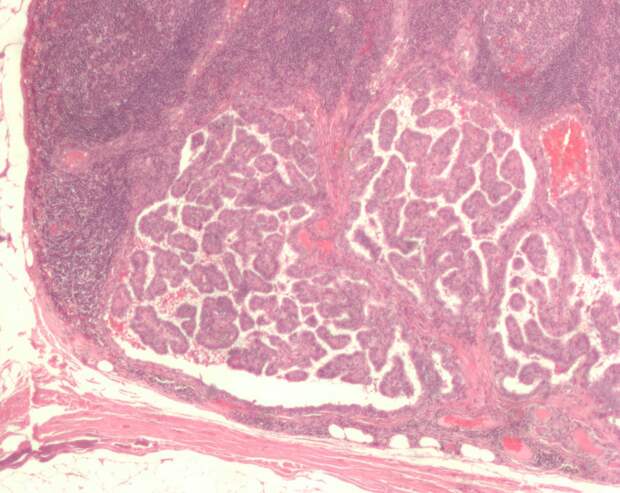

Метастатическое поражение лимфатического узла при папиллярном раке щитовидной железы. Микрофотография / © Nephron / Wikipedia Как сообщает ТАСС, исследователи создали первое в России устройство для лечения онкологии с помощью микроволнового излучения. Ученые уже протестировали прототип в лаборатории.